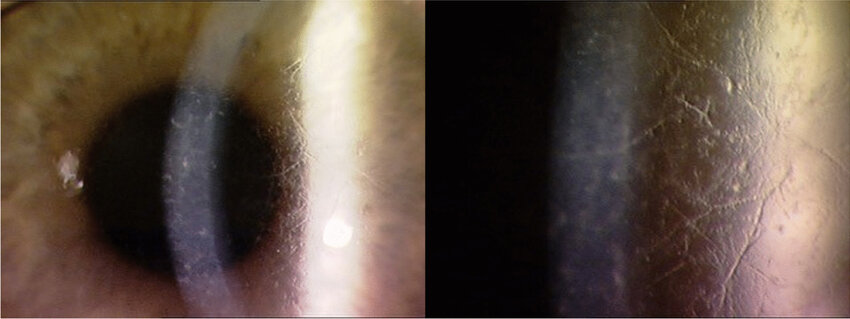

type III 는 상염색체 열성으로 나타나며,

40세 이후 발병하며, 시력저하는 60세 이후 늦게 나타납니다.

각막에는 굵은 형태의 선 침착이 나타나며, 각막 진무름은 발생하지 않습니다.